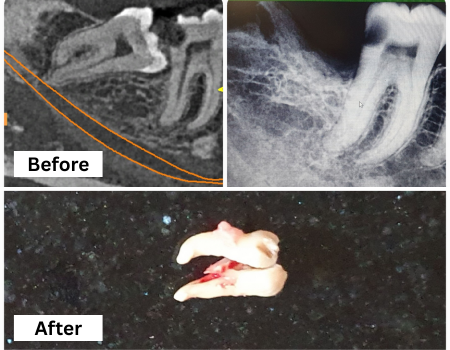

Wisdom Tooth Surgery

Safe, precise removal of impacted or problematic wisdom teeth to prevent pain, infection, and misalignment of surrounding teeth.